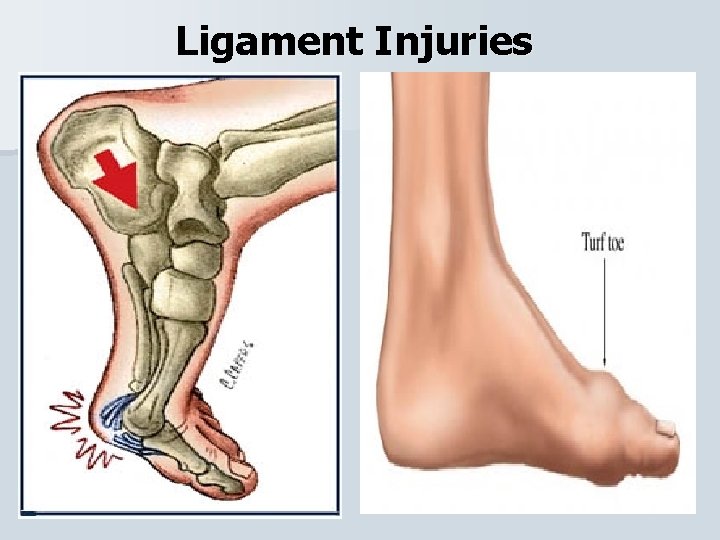

Ligament Injuries

Ligament Injuries

Ligament Injuries

Ligament Injuries

Ligament Injuries

Ligament Injuries